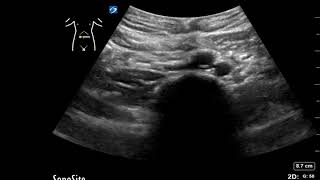

Gulfcoast Ultrasound Institute Instructor Emily Downs, BS, RDMS, RVT, RDCS, RT demonstrates how to evaluate the bifurcation of the aorta at the level of the distal aorta using ultrasound.